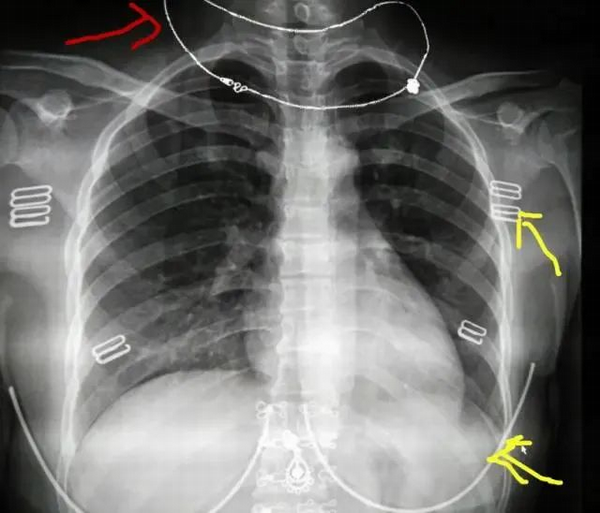

我們看看圖2,這是沒有脫內(nèi)衣拍的。對比第一張,我們看到紅色箭頭的是戴在脖子上的項鏈,黃色箭頭指的是內(nèi)葉的扣子和鋼圈。這些體外的異物跟我們要觀察的骨頭和肺重疊了,如果剛好這些部位有病灶,這些體外的異物就會遮擋了病灶,導(dǎo)致漏診及誤診。